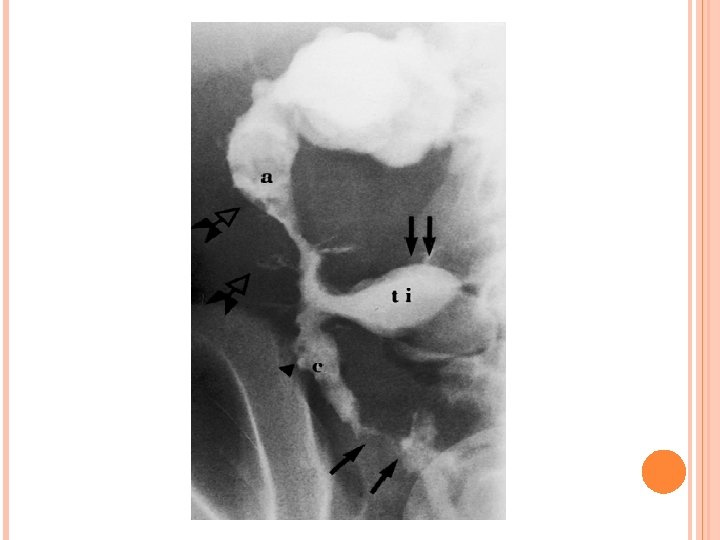

4. Endoscopic and radiologic findings *Small bowel follow-through: show aphthous ulceration and thickened, narrowing of the lumen anywhere in the gastrointestinal tract. Linear ulcers may give a cobblestone appearance to the mucosal surface. Other manifestations on radiographic studies that suggest more severe Crohn disease are fistulas between bowel (enteroenteric or enterocolonic), sinus tracts, and strictures.

Double-contrast barium enema examination in Crohn's colitis demonstrates numerous aphthous ulcers (the tiny spots on the lining of the intestine).

Stricture, terminal ileum - colonoscopy

Severe stenosis of the terminal ileum. Inflammatory effacement of the mucosal folds and small ulcerations characterize the proximal nonstenotic segment.